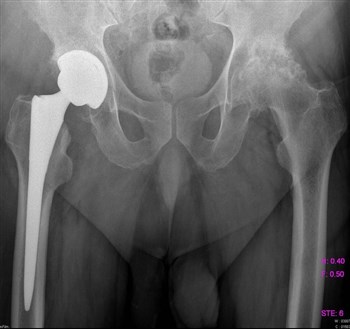

Артроз тазобедренного сустава

Все чаще и чаще пациенты обращаются с жалобами на боли в паху, в колене, иногда на боль в ноге, на скованность движений, нарушение походки.

Как правило, страдают таким недугом женщины после 40 лет.

Боль локализуется в вышеуказанных местах как на одной, так и на обеих ногах.

Проведенная диагностика покажет, в какой стадии находится заболевание, будет дана точная информация о состоянии мягких и костных тканей.

Если заболевание не в хронической форме, или, проще говоря, не запущено, то лечение происходит обычным парацетамолом, без какого-либо хирургического вмешательства. Лечащий доктор назначает курс массажа, лечебной гимнастики, постоянный контроль ортопеда. При ноющих болях прописывается курс болеутоляющих – Кеторол, Диклофенак.

Асептический некроз головки бедра

Все симптомы примерно те же, что и при других заболеваниях, связанных с суставами. Все же важным отличием является постоянная неутихающая боль в бедре, атрофия мышц, укорочение конечности, хромота.

Асептическому некрозу головки бедра подвержены мужчины, особенно после травм – перелома, вывиха или хирургического вмешательства, так как повреждаются сосуды, кровь проходит хуже и они закупориваются тромбами.

В зависимости от запущенности болезни, проводят медикаментозное или хирургическое лечение.

Медикаментозное лечение проводится в том случае, если нет признаков разрушения кости и уровень кальция в организме в пределах нормы.